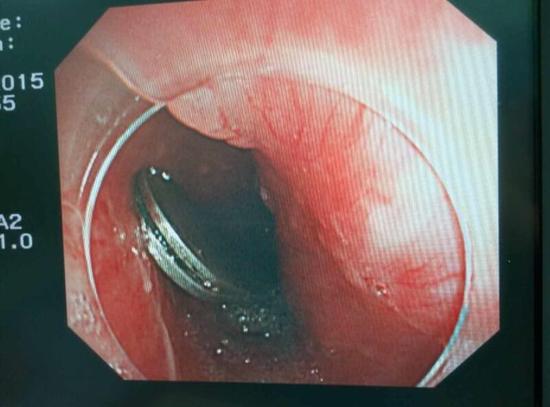

醫(yī)生從華先生胃里取出的鑷子和打火機

手術(shù)中,范醫(yī)生通過胃鏡準(zhǔn)確發(fā)現(xiàn)了胃里的鑷子。但讓他驚訝的是,在華先生胃底竟然還躺著三個被腐蝕了的打火機,打火機的金屬部件都已經(jīng)不見了。

隨后,范醫(yī)生先用圈套器套取出了長10厘米的鑷子,再一個一個地取出了打火機。整個取出過程小心謹慎而又一氣呵成,只用了不到10分鐘。